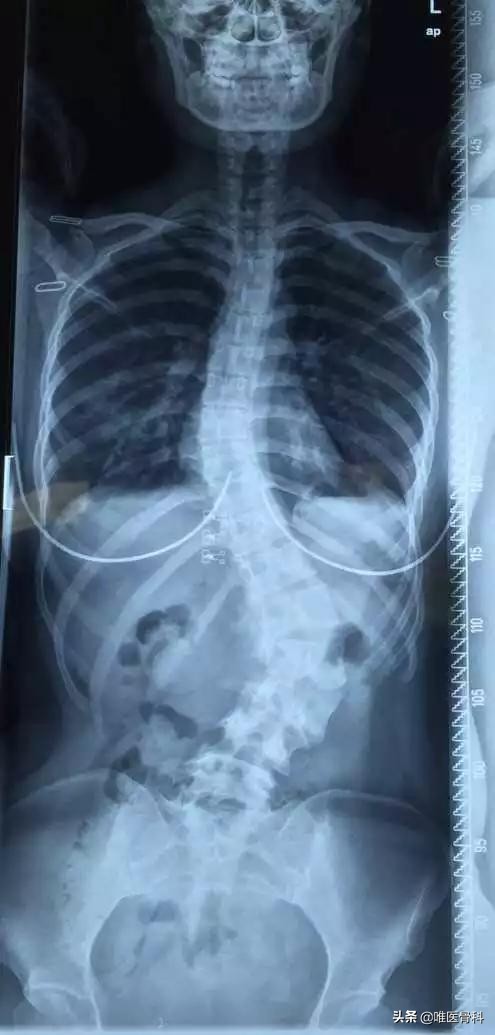

正常人正面看脊柱是一条直线,侧面看它是“S”形曲线。脊柱侧凸时从背面看脊梁骨不是直直的一条线,有偏离中线向侧方的弧形弯曲。

其中最常见的,占总数75%~85%的,是发病原因不清楚的特发性脊柱侧凸。只表现为肩胛骨一高一低,一侧胸部或腰部出现皱褶、皮纹。向前弯腰时背部左右不对称,一侧隆起呈“剃刀背”一样。

凸侧肋骨互相分开,间隙增宽; 凹侧肋骨互相挤在一起,间隙变窄。

这个时候需要站立位下拍摄一个全长脊柱X线片,如果正位X线片显示脊柱有大于10度的侧方弯曲,就可诊断为脊柱侧凸,俗称脊柱侧弯。

一般借助X线片就可以区别侧凸的原因、分类以及弯度、代偿弯、部位、旋转、骨龄等。

常规的X线片应包括站立位的脊柱全长正位和侧位片,上端包括下颈椎、下端包括双侧腰骶关节和髂骨翼。